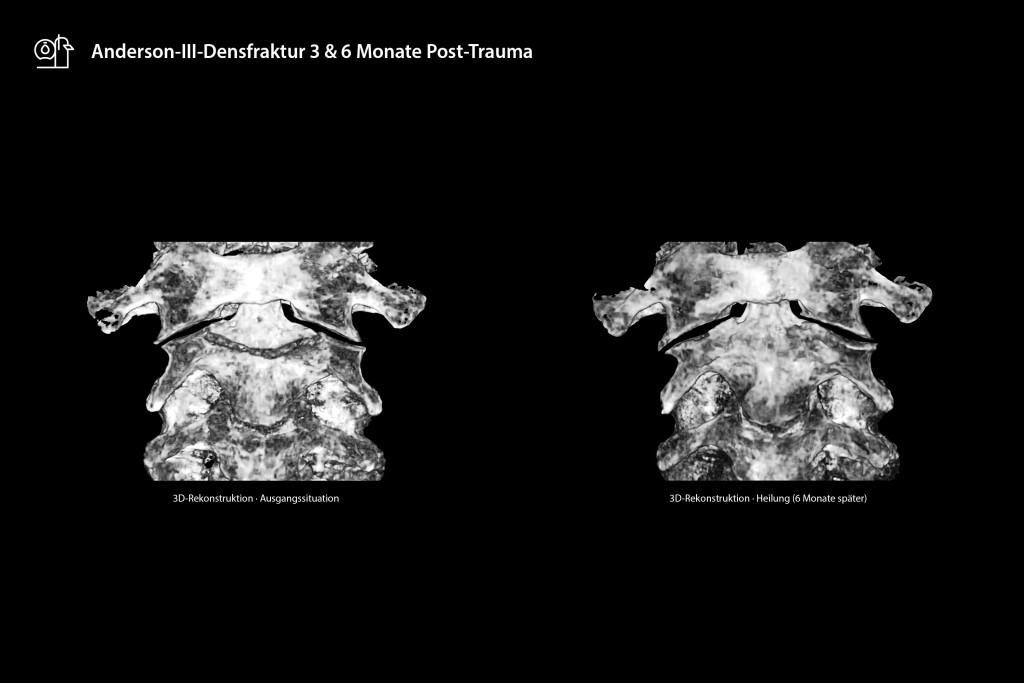

Die erste Kontrolluntersuchung nach drei Monaten mittels SCS MedSeries® H22 DVT, das über ein Super-Ultra-Low-Dose (SULD) Dosisprofil verfügt, dokumentierte eine ungleichmäßige, initial nur zaghaft einsetzende Kallusbildung bei eingeschränkter HWS.

Die hochauflösende 3D-Rekonstruktion des DVT ermöglichte die präzise Darstellung der Frakturspaltmorphologie und frühzeitige Detektion einer drohenden Pseudarthrose, ohne dass eine sofortige operative Intervention erforderlich wurde. Nach ausführlicher Aufklärung über operative Revisionsmöglichkeiten entschied sich der Patient explizit für die Fortsetzung des konservativen Vorgehens unter verlängerter Sportpause und milder Physiotherapie. Die Sechsmonatskontrolle mit dem DVT demonstrierte eine vollständige Frakturdurchbauung mit stabiler Kortikalis und nahezu lückenloser Knochenkontinuität ohne Restinstabilität. Schmerzfreiheit und vollständige Belastbarkeit bestätigten den konservativen Therapieerfolg.

Der angewendete DVT basiert auf der Kegelstrahltechnologie, einem hochauflösenden Detektor sowie einem hochentwickelten Rekonstruktionsalgorithmus und ermöglicht die Akquisition isotroper 3D-Datensätze mit Voxelgrößen bis 0,2 mm. Diese submillimeter-Auflösung übertrifft konventionelle CT-Systeme mit Auflösungen im Praxisalltag von > 1 mm deutlich und eliminiert Partialvolumeneffekte bei der Beurteilung feinster ossärer Strukturen. Ein entscheidender Vorteil liegt in der drastischen Strahlenreduktion: Während eine HWS-CT-Untersuchung etwa 1200 μSv effektive Dosis verursacht, beginnt die Exposition des DVT in diesem Bereich je nach Protokoll bereits ab 29 μSv – und ist damit sogar unter der Strahlenbelastung konventioneller Röntgenaufnahmen in zwei Ebenen (ca. 50 μSv). Diese signifikante Dosisreduktion des DVT im Vergleich zum CT und zu Röntgenaufnahmen in 2 Ebenen rechtfertigt serielle Verlaufskontrollen ohne übermäßige Strahlenexposition analog den Strahlenschutzanforderungen. Die mit dem angewendeten DVT immer einhergehende multiplanare Rekonstruktion ermöglicht zusätzlich die Darstellung anatomischer Strukturen in beliebigen Schnittebenen, während Metallartefakte (in Fällen mit Ostheosynthesematerial im Zielvolumen) im Vergleich zur CT deutlich reduziert auftreten, wodurch u.a. bspw. Grenzflächen zw. Metall und Knochen deutlich besser beurteilt werden können. Besonders bei der Beurteilung der trabekulären Architektur und kortikalen Kontinuität – ob mit oder ohne Metall in diesem Bereich – zeigt der DVT somit seine diagnostische Überlegenheit.